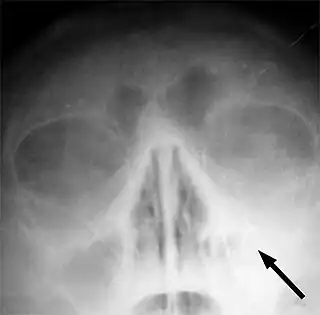

![]() Radiografía que muestra congestión de orificio nasal maxilar izquierdo indicado por una flecha. | ||

En casos con sospecha de complicaciones, que son excepcionales, se pueden realizar exámenes vídeo-endoscópicos, así como un TAC (tomografía axial computarizada). Hay que destacar que la utilización exclusiva de los rayos X para el diagnóstico de las sinusopatías está desaconsejada, debido a la alta tasa de fallos que este examen presenta para los senos faciales, incluyendo falsos positivos.